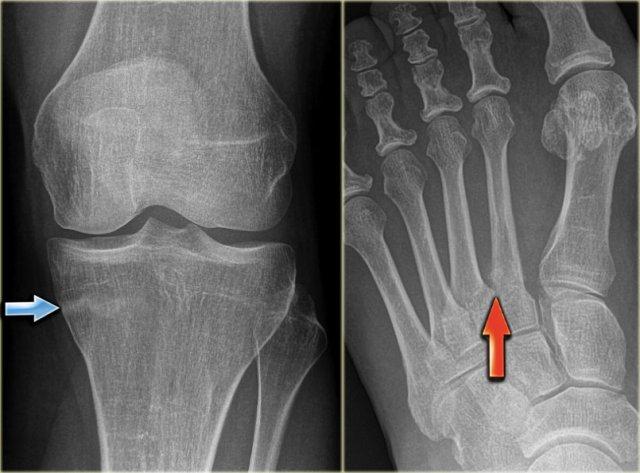

U xơ không cốt hóa (NOF) đôi khi có thể gặp dưới dạng tổn thương xơ cứng một phần hoặc hoàn toàn.

Thông thường, u xơ không cốt hóa biểu hiện là tổn thương tiêu xương lệch tâm, giới hạn rõ, thường được phát hiện tình cờ.

Các tổn thương này thường tự thoái triển và sau đó có thể trở nên xơ cứng.

Các hình ảnh bên trái cho thấy một NOF tiêu xương điển hình với bờ xơ cứng rõ nét.

Hình ảnh bên phải là của một bệnh nhân khác có NOF cũ đã được lấp đầy hoàn toàn.

Đây là phát hiện tình cờ về một số tổn thương xơ cứng lệch tâm ở đầu xa xương đùi.

These are inert filled-in non-ossifying fibromas.

No further examination is needed.